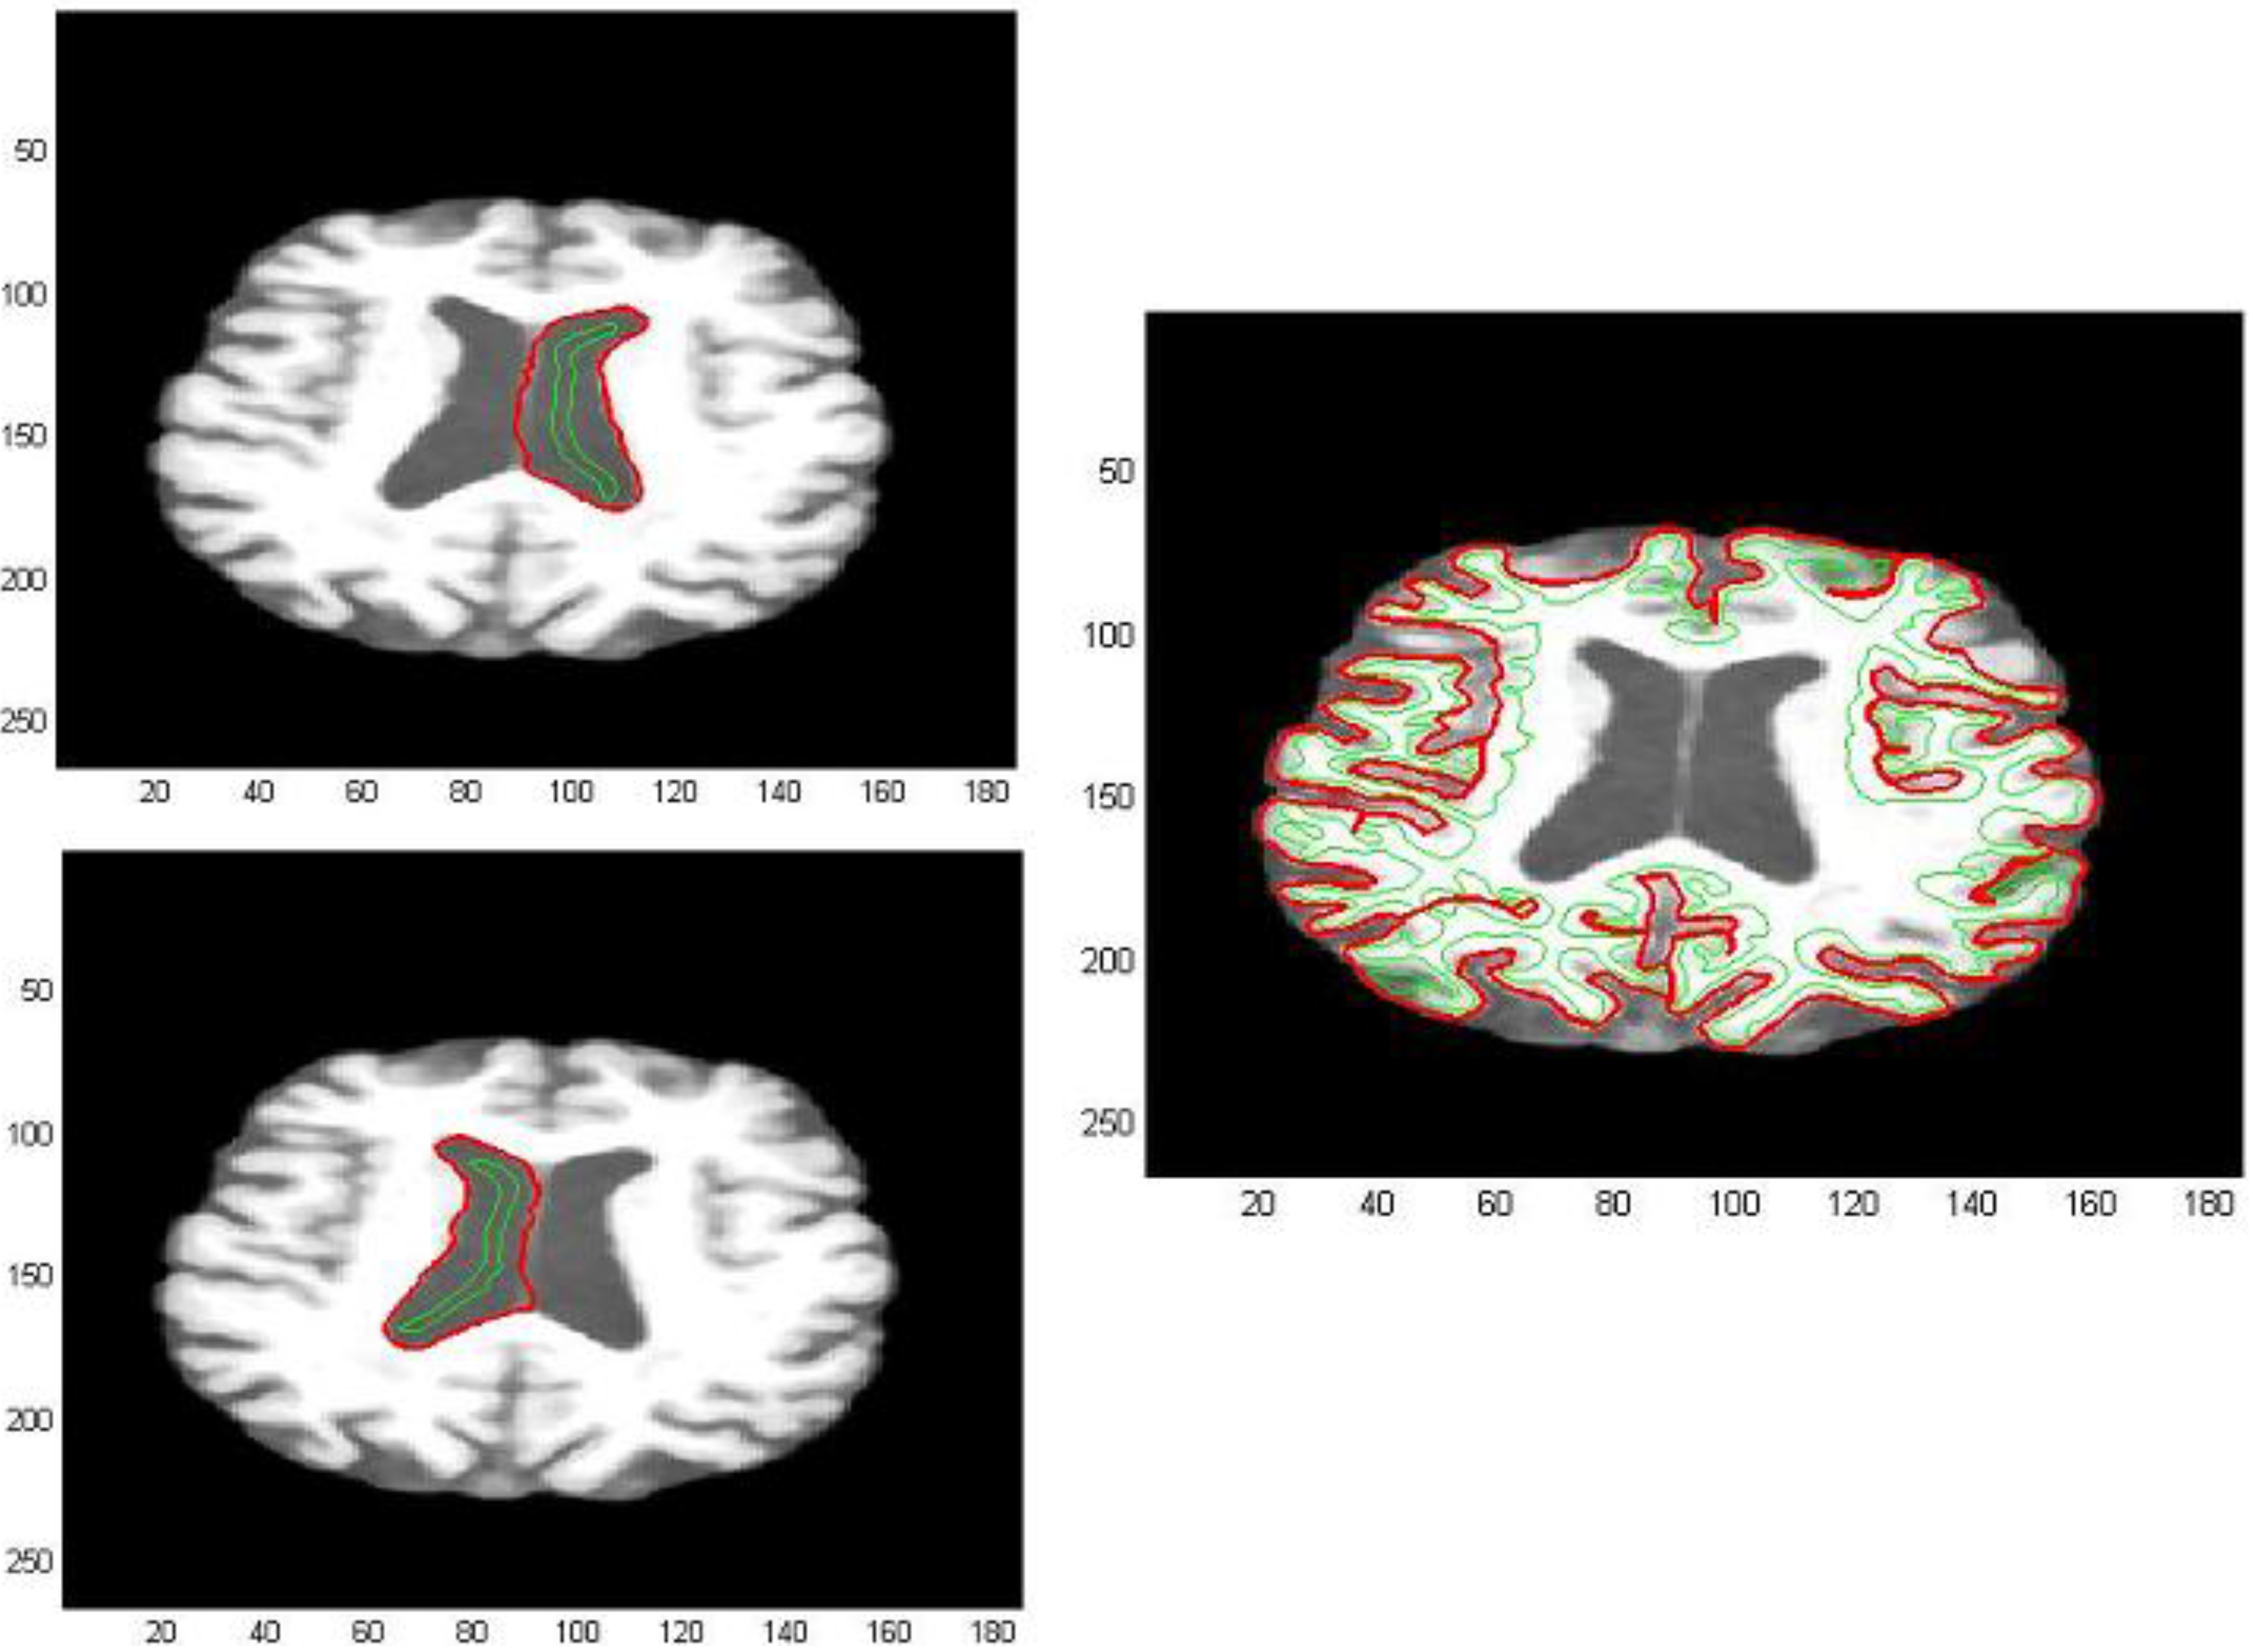

The processed GM and FA images were derived from a dataset composed by a group of 17 patients affected by Alzheimer’s disease and a control group of 11 unities. MRI images were acquired using a 3 Tesla Siemens Impact scanner at the Neuroradiology Unit of the Ospedale Maggiore Borgo Trento, Verona, Italy (2008) with a standard head coil. Axial diffusion tensor images (DTI) were acquired with diffusion encoding gradients applied in thirty noncollinear directions and a b-factor of 1000 s/mm2, plus five images without diffusion weighting. The following parameters were used: TR = 5000 ms, TE = 118 ms, number of slices = 23, slice thickness = 5 mm, slice gap = 1 mm, acquisition matrix = 128 × 128, FOV = 220 mm, the scan duration was 3 min. FA and directional maps for two subjects are shown in Figure 9, the images were realized by using the Software Tools FSL 4.0 (Figure 9 and Figure 10) (Functional Software Library of the FMRIB Centre, Oxford Centre for Functional Magnetic Resonance Imaging of the Brain-Oxford University) [18,19].

Figure 9. FA and directional Maps derived by the Software Tools FSL.

Algorithms 05 00636 g009

Figure 10. Segmentation of a gray matter image (GM), derived by the Software Tools FSL.

Algorithms 05 00636 g010